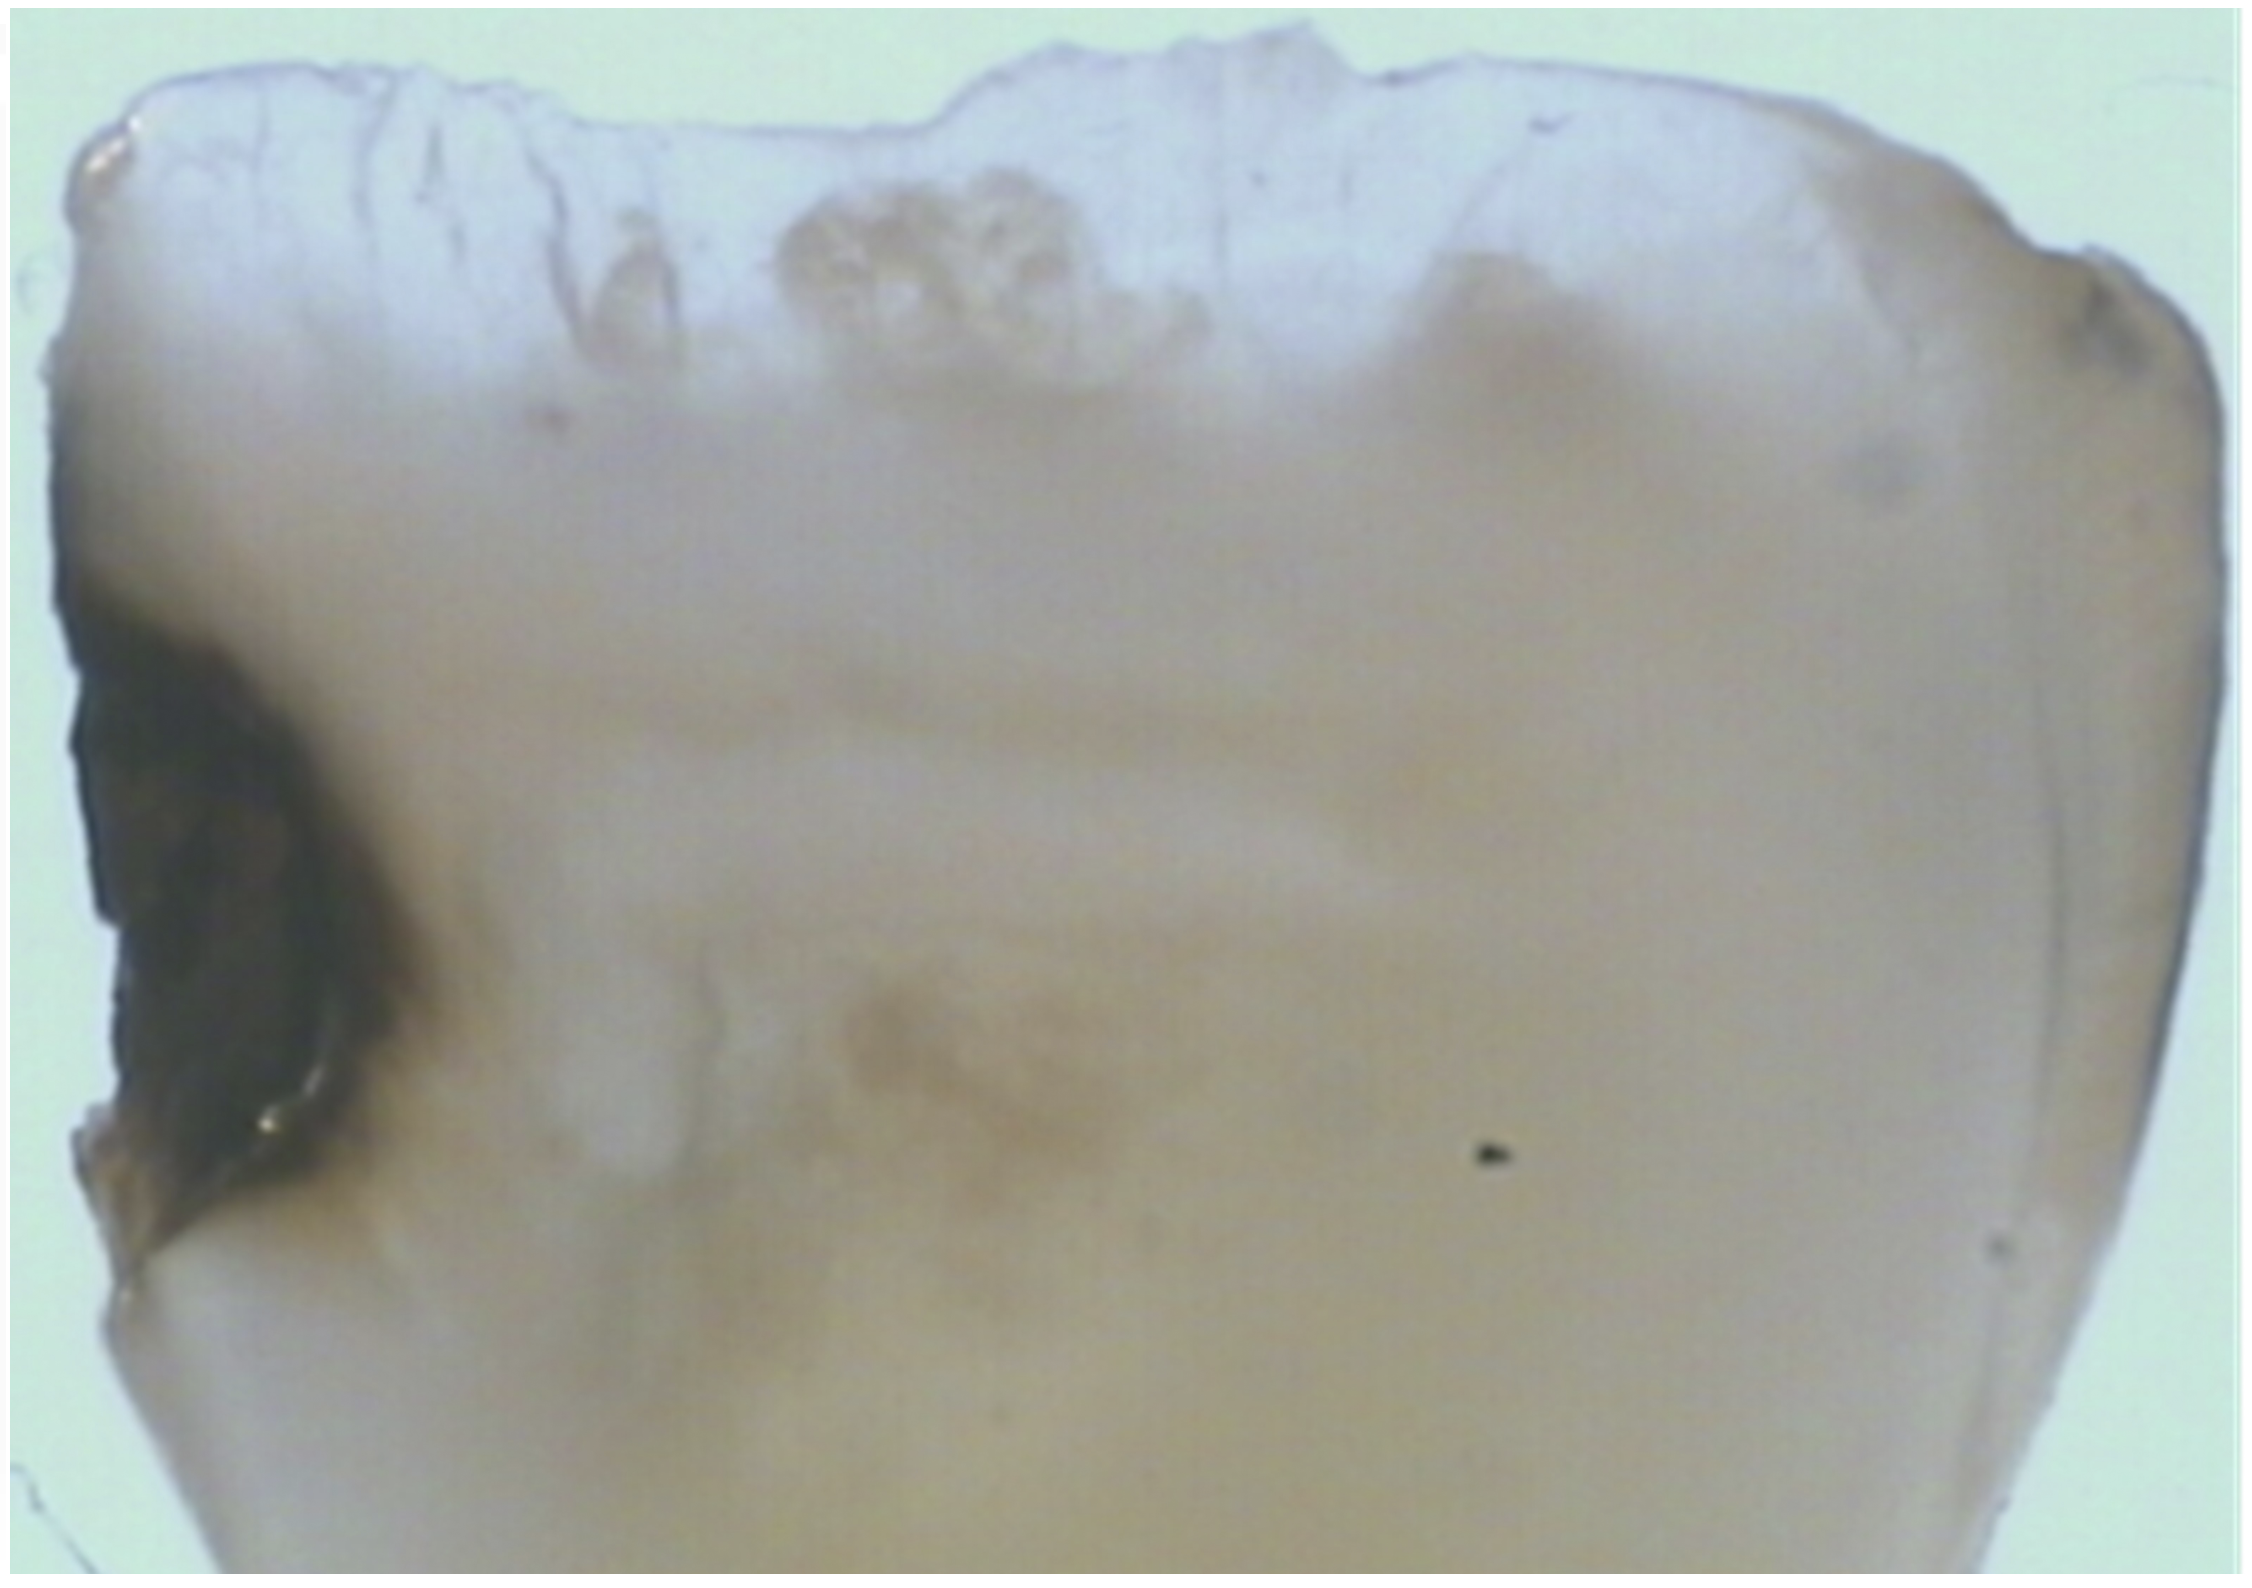

Fig 3. Scanning electron microscope (SEM) images of the dentin carious lesions: surface morphology of arrested carious lesion. (image

from Mei, et al, 2014, ref 21 [reprinted with approval])

There are several advantages of using SDF in dental treatment. First, it showed an antimicrobial activity against mono-species, dual-species, and multi-species cariogenic biofilm.14-16 Silver ions are bactericidal metal cations that inhibit biofilm formation.17 Studies have indicated that silver interacts with sulfhydryl groups of proteins and DNA, thus altering hydrogen bonding and inhibiting respiratory processes, DNA unwinding, cell-wall synthesis, and cell division.18 At the macro level, these interactions affect bacterial killing and inhibit biofilm formation.17 Second, fluoride promotes caries lesion remineralization. Fluoride has been indicated to react with hydroxyapatite and generate calcium fluoride, which is a reservoir of fluoride, and facilitate further remineralization.19 An ex vivo study reported surface microhardness of the surface layer of the arrested caries after SDF applications was comparable with the unaffected sound dentin20 (Figure 1 and Figure 2). This is consistent with another study, in which a high remineralized zone was observed on the surface of arrested caries from exfoliated teeth with SDF treatment21 (Figure 3 and Figure 4). Third, its application procedures are simple and do not require injection or drilling, and the treatment does not involve expensive support infrastructure equipment such as piped water and electricity. The simplicity of the treatment is conducive to treating caries in apprehensive young children who may have intense dental fear, uncooperative patients with special needs, or elderly patients who have difficulty adapting to traditional dental care. It also allows trained workers to deliver the treatment to people who live in the area but who may not be able to easily access dental service.22 Patient compliance and satisfaction is often good when the patient is provided a clear explanation of the treatment outcome.23,24 Finally, the cost of SDF treatment is low and should be affordable in most communities.